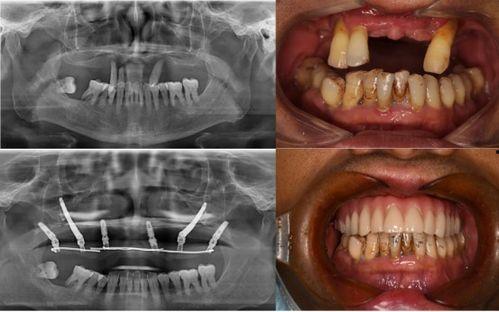

佛山种牙爆料事件最新情况,最新进展与各方回应梳理

最近佛山那边的种牙事件可是闹得沸沸扬扬的,咱们得好好来聊聊这个话题。你有没有听说,佛山某口腔医院因为种牙问题引发了一场不小的风波?别急,让我带你一探究竟,看看这背后到底隐藏着怎样的秘密。一、事件起因:患者反映种牙后问题不断话...